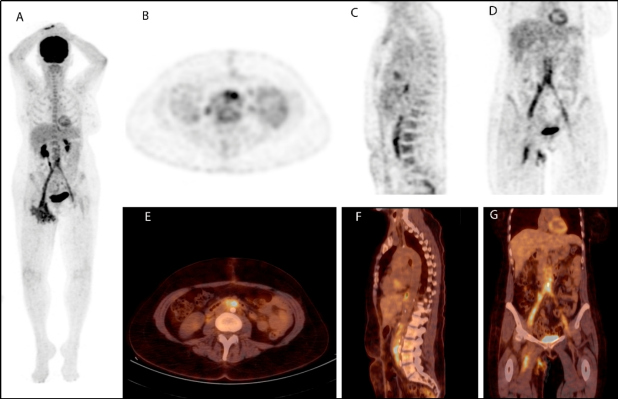

A fin de valorar la extensión de la infección y la posible afectación del by-pass, se realizó en primer lugar una angio-TC donde se evidencia permeabilidad del by-pass y líquido libre periprotésico en su vertiente distal derecha que conecta con la colección inguinal derecha de aproximadamente 1,8 x 3,8 cm. Posteriormente se realiza PET/TC con 18F-FDG a los 120 min de la administración IV de 160 MBq de 18F-FDG que muestra un intenso consumo lineal, homogéneo y difuso en todo el trayecto protésico, sugestivo de infección del mismo (figs. 1 y 2).